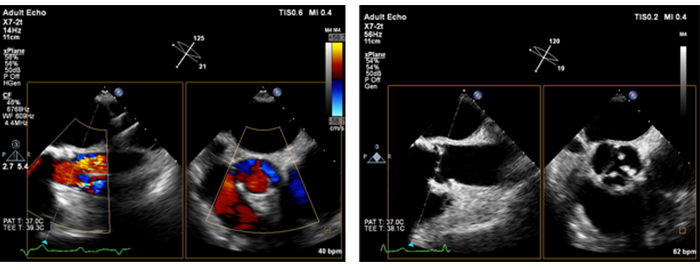

Obrazowanie Live xPlane z wykorzystaniem głowicy ultrasonograficznej xMATRIX W tym trybie obrazowania jednocześnie rekonstruowane są dwie płaszczyzny w pełnej rozdzielczości, co pozwala na uzyskanie dwukrotnie większej ilości informacji klinicznych w czasie odpowiadającym tradycyjnemu obrazowaniu 2D.

W badaniach kardiologicznych obrazowanie Live xPlane umożliwia jednoczesną akwizycję dwóch płaszczyzn na podstawie tego samego cyklu pracy serca, co pozwala na szybkie i skuteczne uzyskanie najistotniejszych informacji.